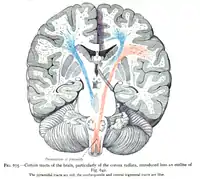

| Corona radiata | |

In neuroanatomy, the corona radiata is a white matter sheet that continues inferiorly as the internal capsule and superiorly as the centrum semiovale. This sheet of both ascending and descending axons carries most of the neural traffic from and to the cerebral cortex. The corona radiata is associated with the corticopontine tract, the corticobulbar tract, and the corticospinal tract.

Projection fibers are afferents carrying information to the cerebral cortex, and efferents carrying information away from it. The most prominent projection fibers are the corona radiata, which radiate out from the cortex and then come together in the brain stem. The projection fibers that make up the corona radiata also radiate out of the brain stem via the internal capsule. Cerebral white matter is commonly regarded today as an intricately organized system of fasciculi that facilitate the highest expression of cerebral activity.